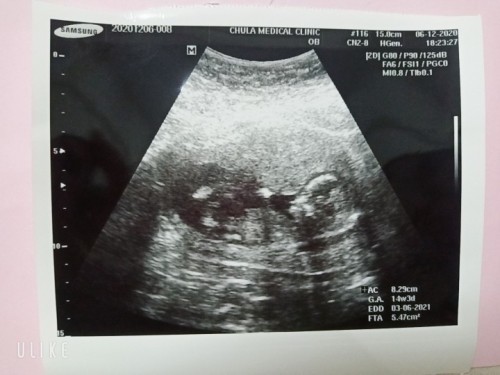

ค่ะ ตอนนี้ไม่รู้ว่าหนูน้อยเพศอะไร แต่ก็จะติดตามคุณแม่ศิวพรรอดูว่าเราจะได้ลูกเพศอะไรกันนะคะ